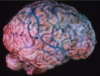

Subarachnoid hemorrhage

Caused by Berry aneurysm

What is this. What are the complications of this?

Berry aneurysm

Rebleeding

Vasospasm

Fibrosis of subarachnoid space